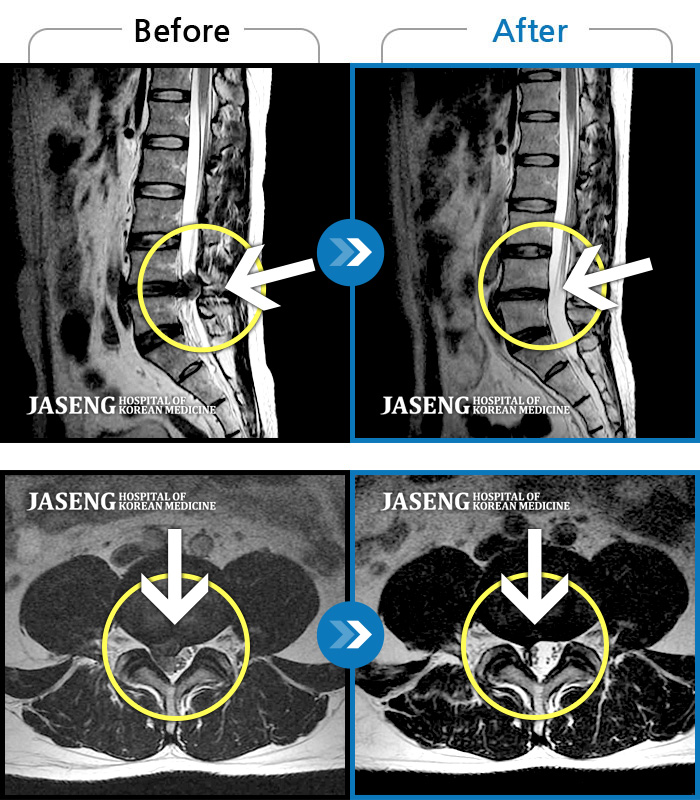

목디스크

대구 · 윤대연 원장

목부터 양어깨 손가락까지 저림, 야간통

촬영시기

2015.05.13 ~ 2016.06.27

2016.12.28